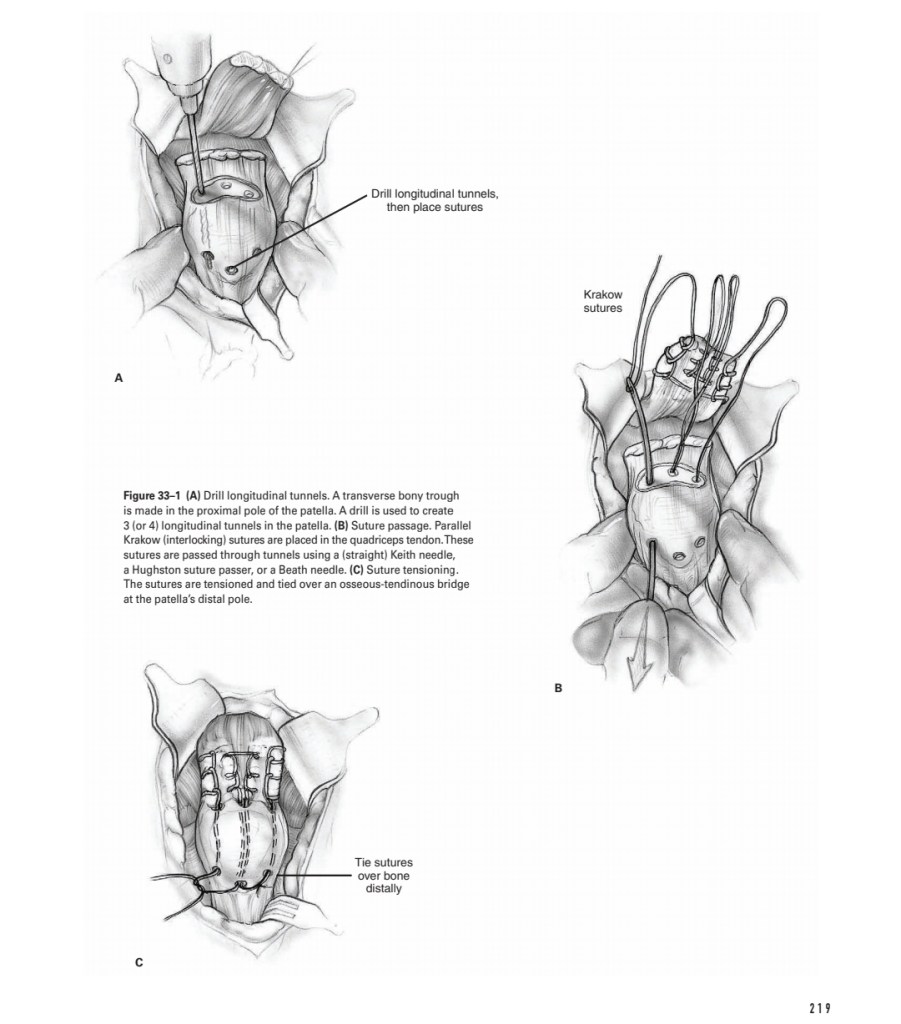

Lecture Knee dislocation & tendon injuries

Lecture Knee dislocation & tendon injuries